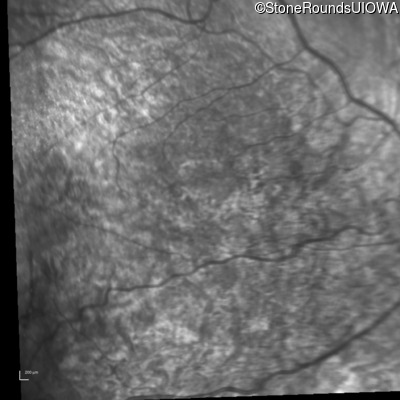

Infrared Fundus Photograph - Left - 20/32 +1

Exemplar